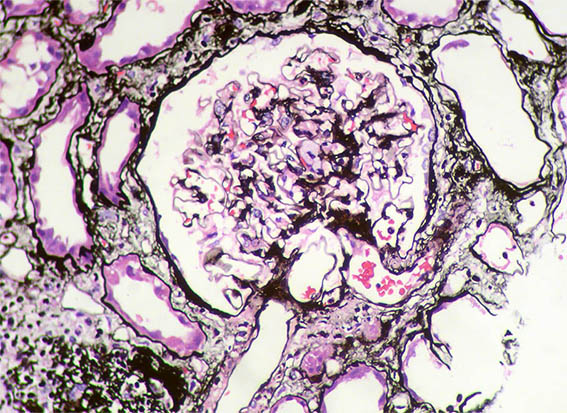

Figure 9. Methenamine-silver stain, X400.

Figure 10. Diffuse podocyte damage, with microvillous transformation of the podocyte cytoplasm. EM, original magnification, X2,100.